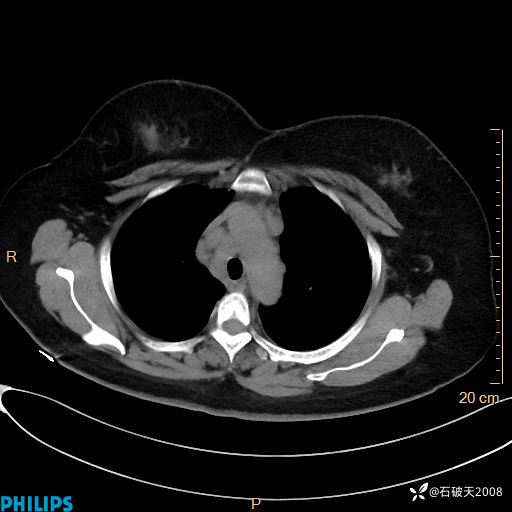

肺窗